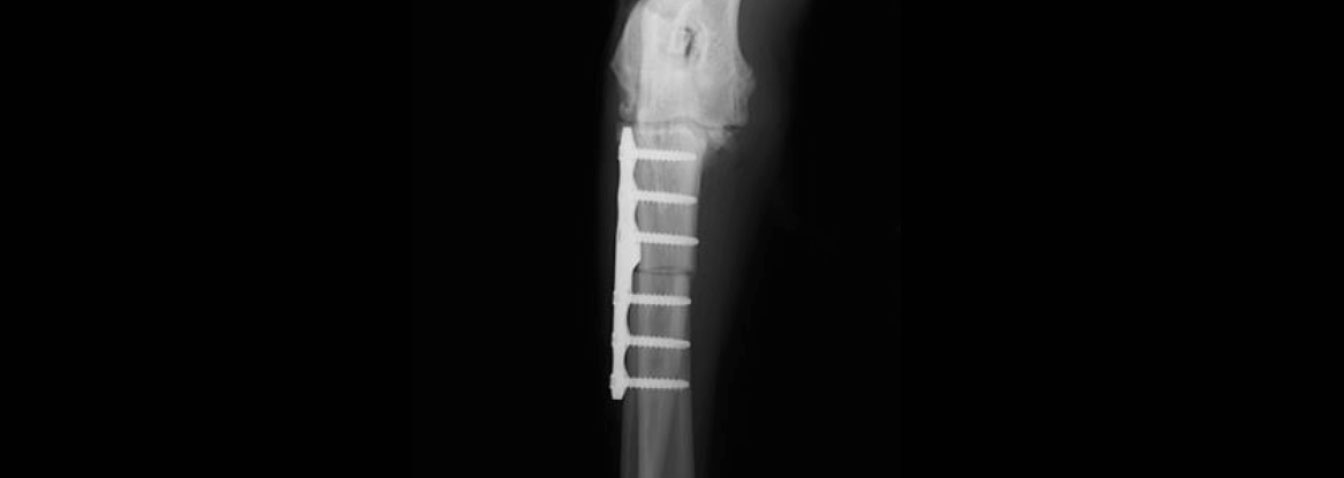

近位尺骨外反骨切り術

前肢尺骨を骨切りして角度を矯正、荷重バランスを均等に。

PAUL法では尺骨を特殊な角度で骨切りし、肘関節の内側と外側に均等に荷重がかかるよう、専用の金属板と骨ネジで固定して角度矯正を行います。軟骨は一度消失すると再生されないので、外側の軟骨に損傷が起こる前に手術を行う必要があります。

肘関節の接触力学が内側に崩れて傾いた尺骨の近位(肘付近)を骨切りし、角度の偏りをなくすことで荷重バランスを均衡化させます。術前・術後を比較すると、上腕骨側からの負荷が内側に逃げ、着地の際の反力も受け止められていない状態から、力の受け渡しが中心軸に沿って正しく行われるようになっているのがわかります。